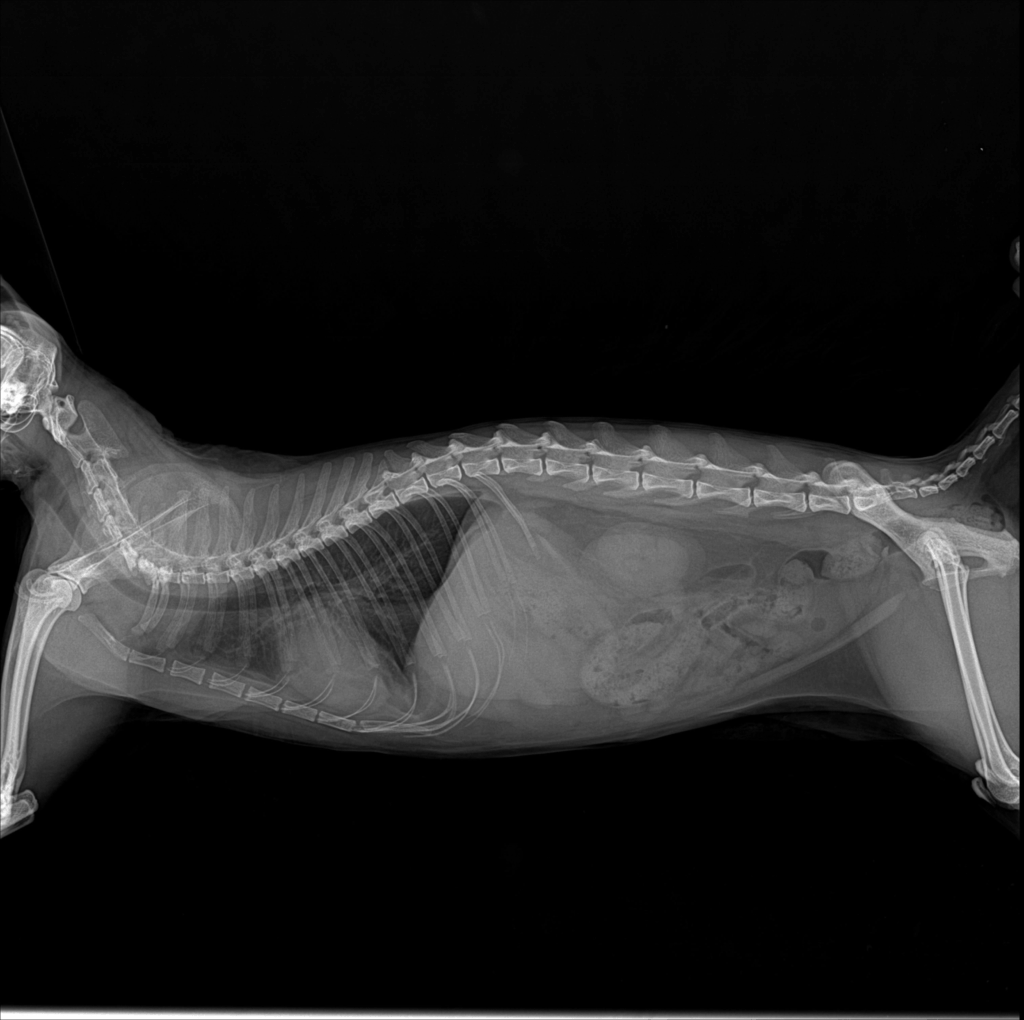

엑스레이 검사에서 방광이 정상보다 크게 팽대된 상태가 확인되었습니다.

환자 방사선 사진 / 출처: 미래동물의료센터

입원 5일차에 요도 카테터를 제거한 뒤 자발 배뇨 여부를 집중적으로 관찰하고, 방사선 검사를 통해 방광과 요도의 상태를 다시 한 번 확인했습니다. 원내 모니터링 결과 자발 배뇨가 원활하게 이루어지는 것이 확인되어 퇴원이 결정되었습니다.

환자 퇴원 직전 카테터 제거 후 엑스레이 사진 / 출처: 미래동물의료센터